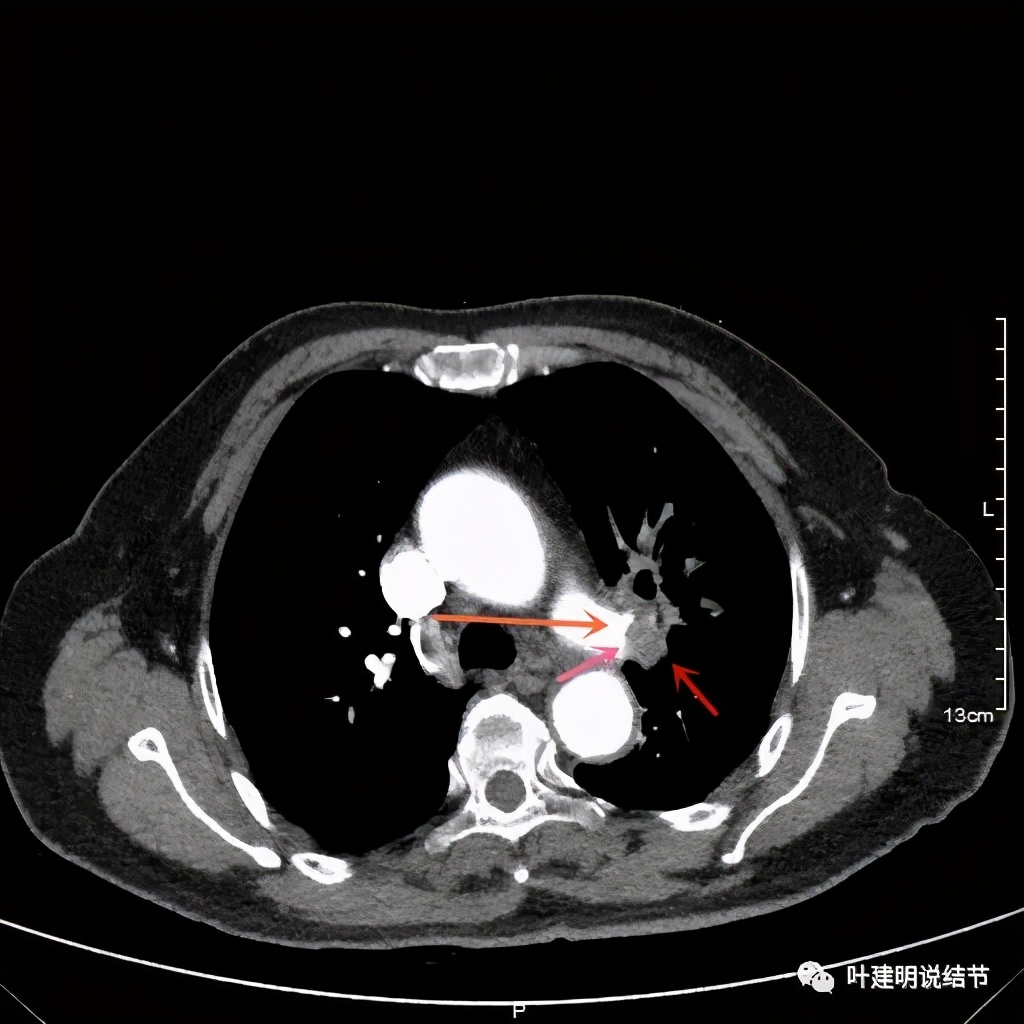

上图桔色箭头示左肺动脉分支处仍被软组织(原肿瘤所在)包绕,粉色箭头示肺动脉仍与肿瘤处关系密切

上图也示桔色箭头示左肺动脉分支处仍被软组织(原肿瘤所在)包绕,粉色箭头示肺动脉仍与肿瘤处关系密切